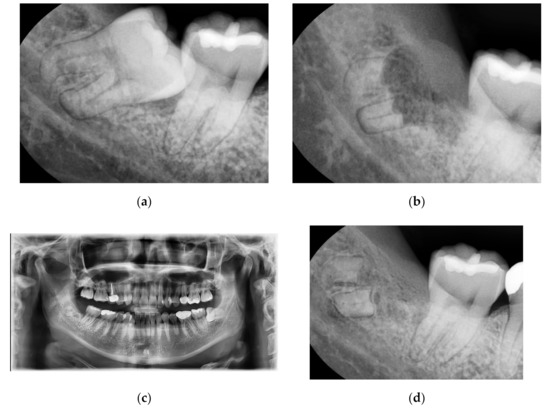

3.2. Case No. 2: Intentional Coronectomy

A 25-year-old female patient without systemic diseases had the right mandibular wisdom tooth extracted three years ago due to mesioangulation, which caused pain and sensitivity to its adjacent second molar in addition to recurrent inflammation in the gingiva and pericoronitis (Figure 2a).

The main clinician (Kim) decided to perform a coronectomy to avoid any risk of nerve damage in this young patient who had odontophobia; therefore, the surgical procedure was fast and without bone cuts. Using CBCT, the position of the apical third of the roots was confirmed to be very close to the inferior alveolar nerve.

After 14 days, the patient was recalled for suture thread removal, where she was free of pain (VAS score “2”) and showed no sign of fear while in the dental office (Figure 2b). Three years later, the patient came again to the dental clinic for a dental check-up and for the extraction of the left mandibular wisdom tooth, and she reported no sign of pain or disturbance in the area of the right mandibular wisdom tooth. Figure 2c shows the complete formation of the alveolar cortical bone.

Figure 2. (a): Right mandibular wisdom with pain and sensivity due to pericoronitis. (b): X-ray after 14 days from the coronectomy. (c): OPT after three years of follow-up.